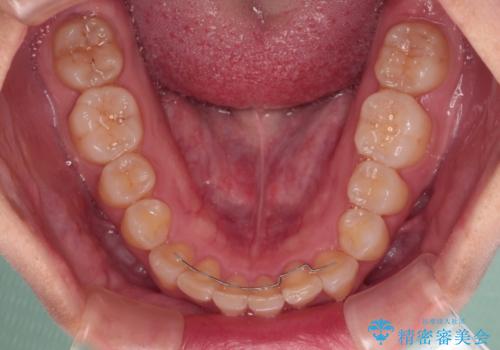

- 上の前歯の出っ歯と前歯の深い咬み合わせを治したいとのことで来院された患者様です。

上顎の歯は後方移動とIPR(歯と歯の間を削る)によって口元が引っ込むように、下顎は歯列全体の拡大とIPRによって上顎とバランスよく咬み合うように設計し、インビザラインにより治療を行うこととしました。

上顎歯列の後方への移動量が多く、右側の奥歯の咬み合わせを改善する必要もあったため、治療には長期間を要しました。